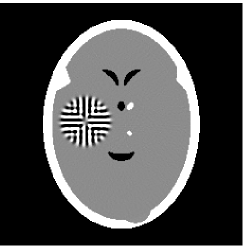

Noised projection data: For the noised projection data, the iteration processes were terminated when for 82 and 112 projections. The reconstruction images were given in Fig. 7. Table 4 showed the MSEs, iterations and running time of program of the results of images in Fig. 7.

![]() |

| TV-S | TV-S |

| TV-PPS | TV-PPS |

| Algorithm | TVS | TV-PPS | TVS | TV-PPS |

|---|---|---|---|---|

| projections | 112 | 112 | 82 | 82 |

| iterations | 3 | 7 | 13 | 13 |

| MSEs | 0.0102 | 0.0080 | 0.0164 | 0.0158 |

| RT(min) | 2.0529 | 5.1975 | 10.382 | 9.1644 |

By comparing the images in Fig. 6, 7 and numbers in Table 3, 4, we can obtain the same conclusions that the proposed perturbation can not only improve qualities of reconstructed images, but also can accelerate the convergent speed. However, we can observe that the reconstruction images suffer from artifacts regardless of the classic and the proposed algorithm when the projections is inadequate.